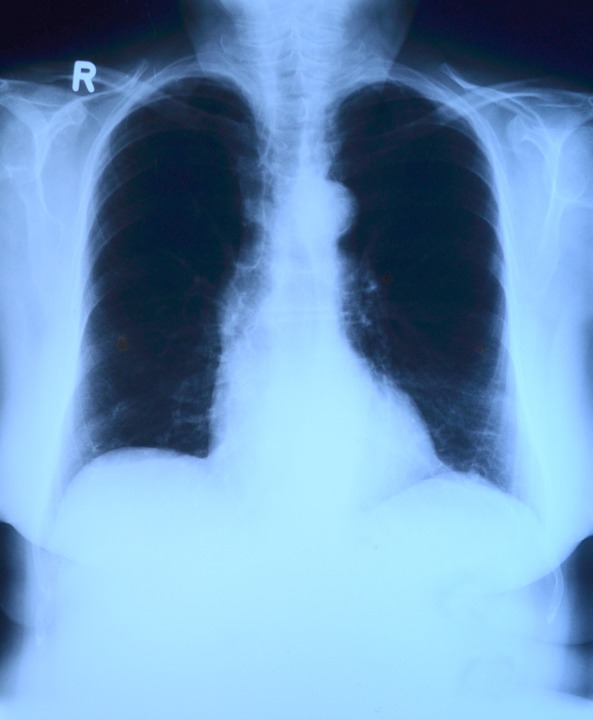

Ο καρκίνος των πνευμόνων είναι η συνηθέστερη αιτία θανάτου από καρκίνο σε πολλές χώρες. Ο καπνός, που περιέχει χιλιάδες χημικές ουσίες, κάνει ζημιά στο DNA των κυττάρων των πνευμόνων, δημιουργώντας έτσι γενετικά σφάλματα, μερικά από τα οποία είναι εν δυνάμει καρκινογόνα.

Οι ερευνητές, με επικεφαλής τη δρα Κέιτ Γκάουερς του Πανεπιστημιακού Κολλεγίου του Λονδίνου (UCL) και τον δρα Πίτερ Κάμπελ του Ινστιτούτου Wellcome Sanger, που έκαναν τη σχετική δημοσίευση στο περιοδικό «Nature», μελέτησαν για πρώτη φορά τις γενετικές επιπτώσεις του καπνίσματος σε βιοψίες πνευμόνων 16 ανθρώπων, καπνιστών, μη και πρώην.

Διαπιστώθηκε ότι, παρόλο που δεν ήσαν καρκινικά, πάνω από εννέα στα δέκα κύτταρα των πνευμόνων των καπνιστών έχουν έως 10.000 έξτρα γενετικές μεταλλάξεις σε σχέση με τους μη καπνιστές, οι οποίες προκλήθηκαν από τις χημικές ουσίες στον καπνό. Πάνω από ένα στα τέσσερα από αυτά τα κύτταρα είχαν τουλάχιστον μία μετάλλαξη που θα μπορούσε να εξελιχθεί σε καρκίνο, πράγμα που εξηγεί γιατί ο κίνδυνος καρκίνου των πνευμόνων είναι τόσο μεγαλύτερος στους καπνιστές.